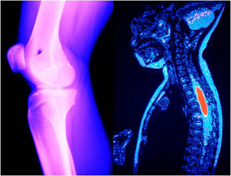

レントゲン(X線)の発明は体の中を透かして見るという、まさに見えなかったものが見えるようになりました。そうして病気が見つかり、直すこともできるようになりました。